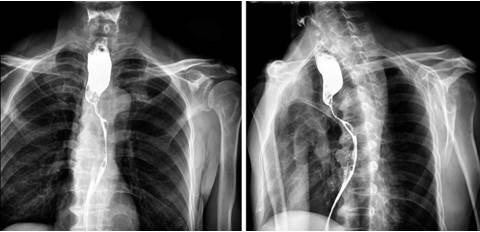

细数最新一代DR能实现的功能:高清拍片像素越来越高、透视点片能实现毫秒级切换、针对各部位的造影如泌尿系统造影、消化道造影均能操作、以及减少操作医生误差的自动曝光控制功能,可以说最新一代的DR推动了基础影像检查的进步。在最新一代DR的几项“绝技”中,有一项是不可忽略的,那便是——视频保存回放功能。

简单介绍一下视频保存回放功能。在使用DR进行透视及造影检查后,软件会自动保存检查视频,医生可以在任意时间调取视频重复观看。

食管造影是放射科常做的造影检查之一,广泛应用于肿瘤上、下范围确定,食管异物检查等食管疾病。在做食管造影时,医生需要观察食管壁、食管粘膜样变情况,同时要在斜位对食管做全景观察。为了有效给医生提供前期的病理参考性信息,还需观察是否有细小溃疡、炎症,所以医生需要观察的信息量很大。而食管造影检查中钡剂流完的时长仅有6-7秒,对于经验丰富的医生来说,都需要重复观看造影过程1-2次,才能做出精准的诊断。而如果机器没有视频保存回放功能,医生很容易就因为造影剂流速过快造成观察不到位,错过大量信息。因此,虽说食管造影检查简单,但由于目前喉癌、食管癌病发率高,拥有视频保存回放功能可以更精细的观察食管更多的信息,针对癌症可以做出提前预判,针对病灶可以做出精准诊断。

放射科室人员的更新换代是很正常的,大部分医院的放射科都有年轻医生。在做一些造影检查时,比如全消化道造影,医生需要观察整个消化道的情况,从食道到直肠末端大体的二维信息,观察肠道是否通畅、是否有梗阻、炎症;还要关注很多细节,包括胃部幽门区域、十二指肠、小肠、结肠。对于经验不足的年轻医生来说,很容易漏过一些病症细节,得到不准确的检查结论。如果没有视频保存回放功能,而病人的身体确实有对应此部位的不良反应,那就只能再重新做一次检查,病人不仅需要二次缴费,更加不利的是,病人要再吃一次射线。或者是没有对病人重新检查,则可能造成一次漏诊病例。